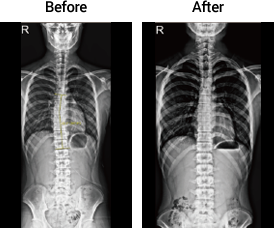

측만증

18세 여성

회전변형

18세 남성